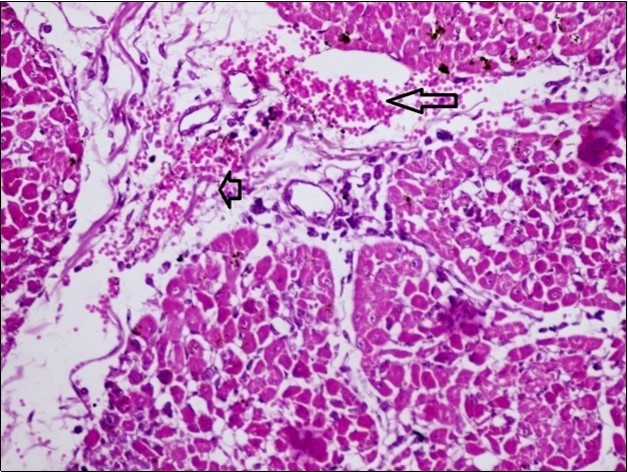

Figure 8.spleen (dead cattle less than 1 year old) showed severe depletion of lymphocytes with necrosis of endothelial lining or splenic arterioles (arrows). (Hematoxylin and fuchsin X 60)

Figure 10.Heart (dead cattle less than 1 year old) showed area of extravasated blood with few inflammatory WBCs (arrows). (Hematoxylin and fuchsin X 40)

Figure 11.heart (dead cattle less than 1 year old) showed vesicular nuclei of myocytes which suffering hydropic degeneration. Some inflammatory cells (neutrophils, esinophils, lymphocytes) substitute an area of necrosis inside myocardium bundles (arrows). (H &E, X 40)